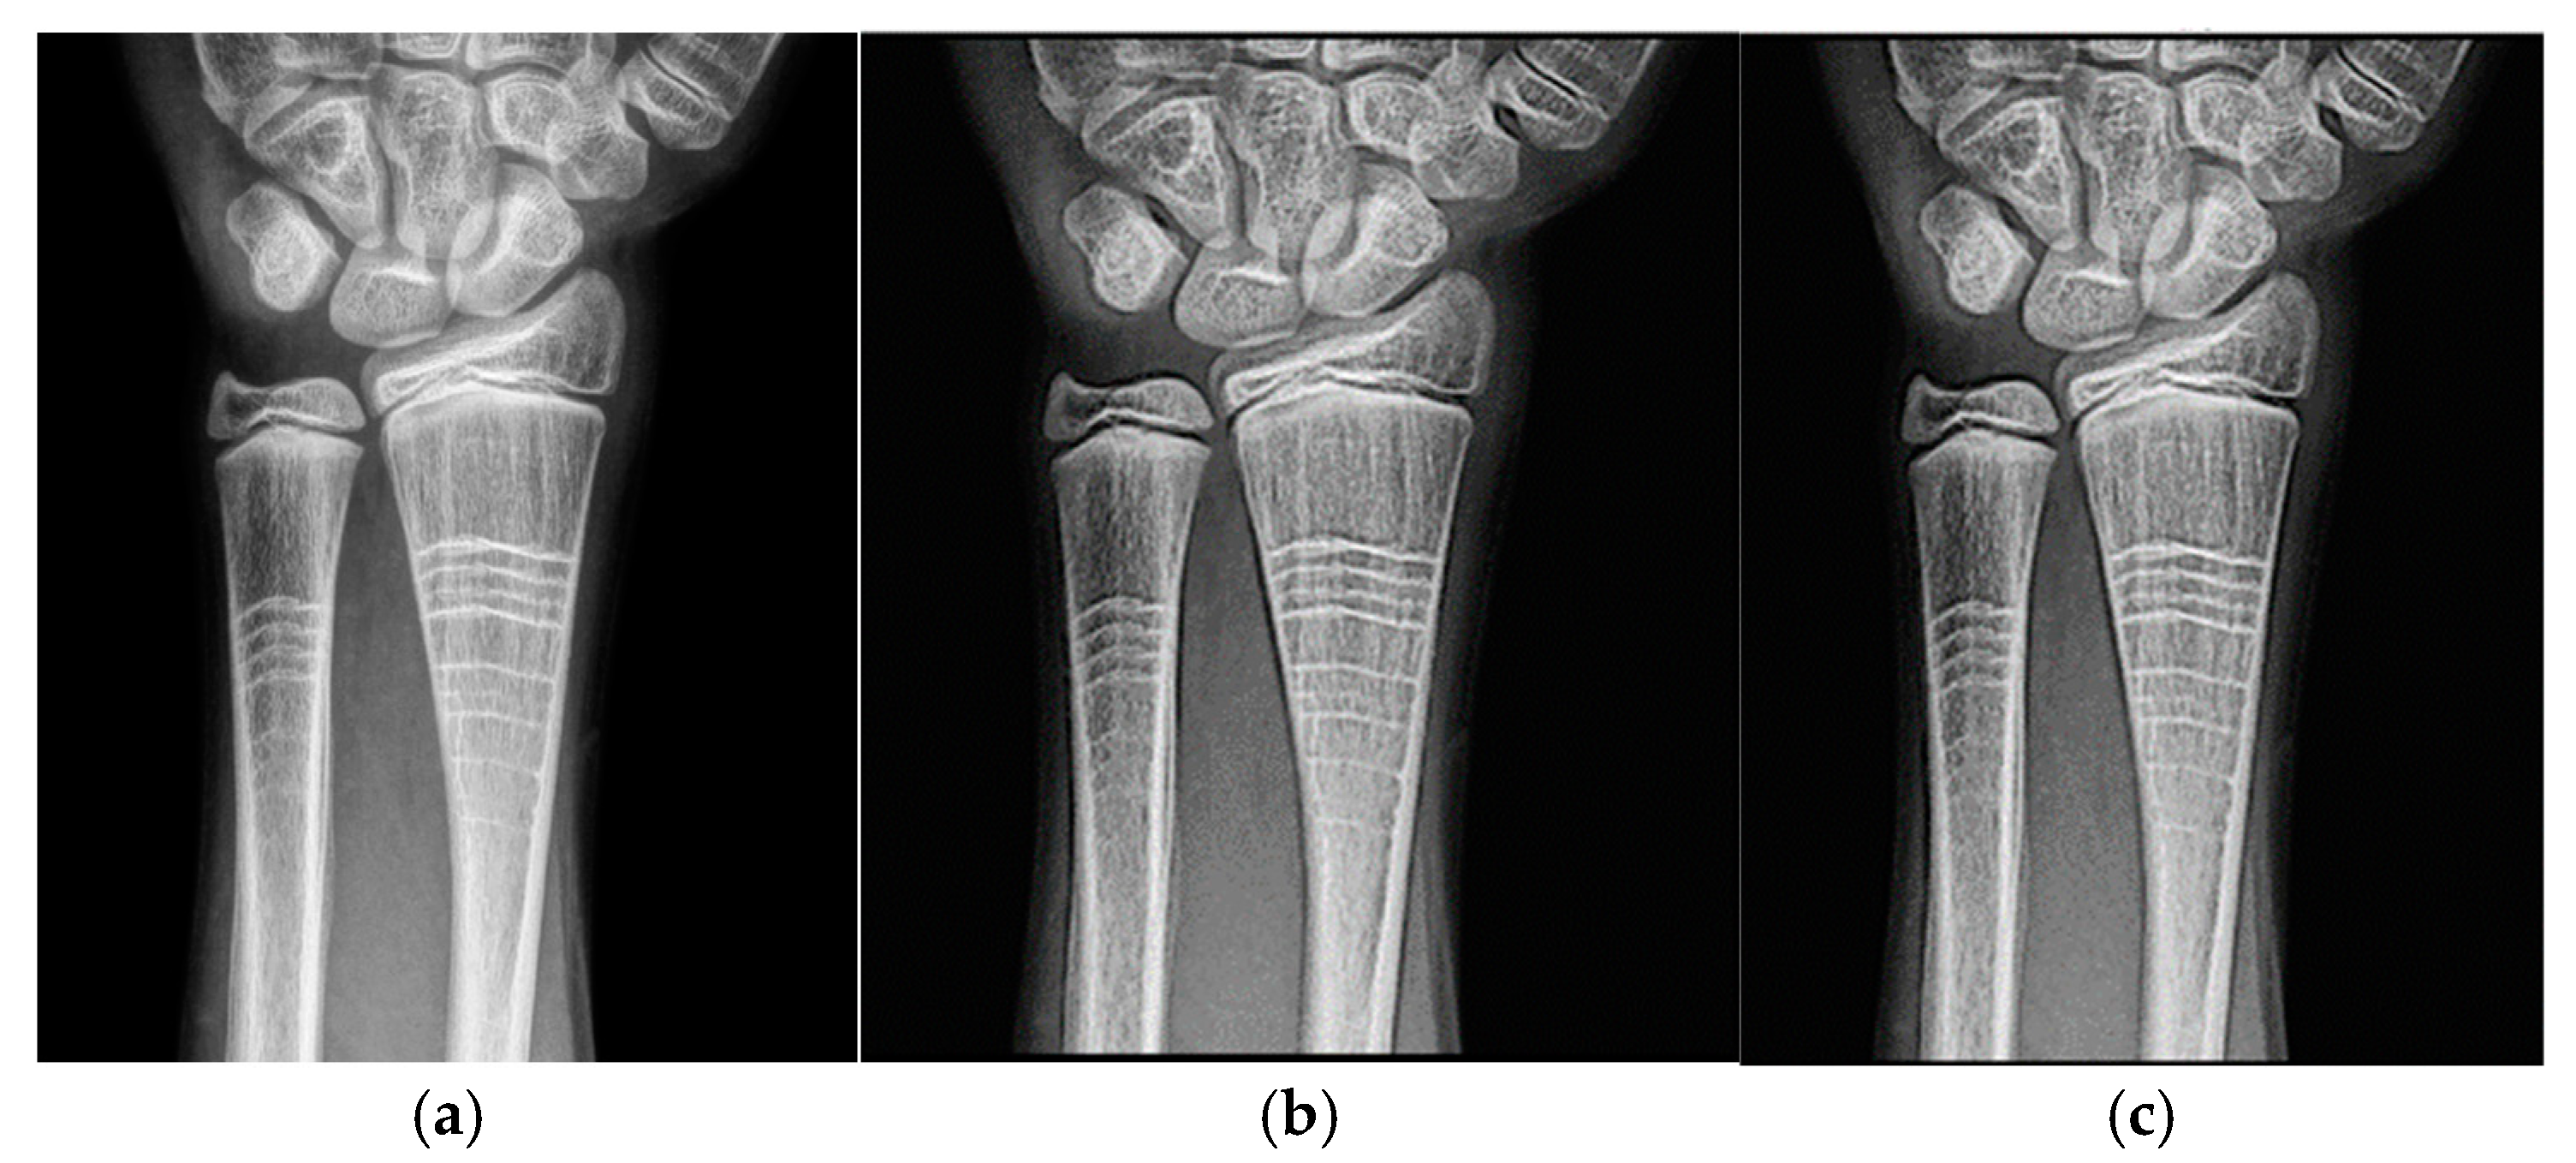

Wrist radiographic images processed with values close to d = 1.4 (Figure 7) show greater sharpness and detail, as in the case of the knee. The contrast improves steadily up to d = 1.4, as shown in Table 4. Entropy increases slightly, maintaining noise levels. The maximum contrast value is 3.76 at d = 4.4, which is a 38% improvement. Visual inspection confirms that the filter works in small, highly detailed regions.

Figure 8 and Figure 9 present the behavior of contrast and entropy for wrist images as a function of d. In the graph, Filter 1: Cream (red) and Filter 2: Bosso (blue). These figures demonstrate the effectiveness of the double filter in enhancing wrist X-rays.

Table 4 shows the contrast and entropy values for different d values in the wrist image. As with the knee image, both filters achieve an increase in contrast, with a crossing of the curves earlier than in other cases. Entropy also presents an ascent but maintains reasonable values.

Figure 7. Original image (a) obtained from the wrist for d = 1.4, with filter 1 (b) and filter 2 (c).